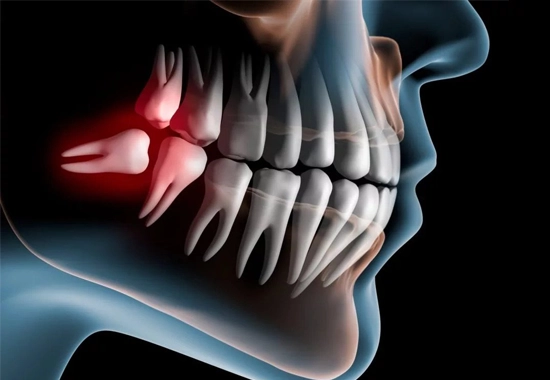

Wisdom Teeth Impaction

When wisdom teeth become impacted, they can cause a number of detrimental symptoms, including severe pain, swelling in the gums or around the jaws, bleeding gums, bad breath, strange tastes when eating, and even headaches. With that in mind, some individuals who have impacted wisdom teeth experience no symptoms at all.

Wisdom teeth impaction can occur to varying degrees. Soft tissue impaction is present when the top portion of the tooth (the crown) has come through the bone but is fully or substantially covered by the gum. A partial bony impaction involves a wisdom tooth that has partially erupted, but is still primarily below the gum tissue and inside the jawbone. A full bony impaction is a tooth that has not erupted and is completely covered by the jawbone.